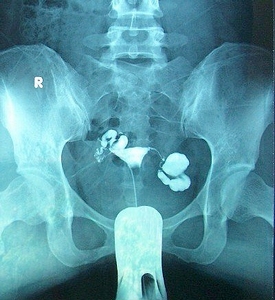

输卵管碘海醇造影图